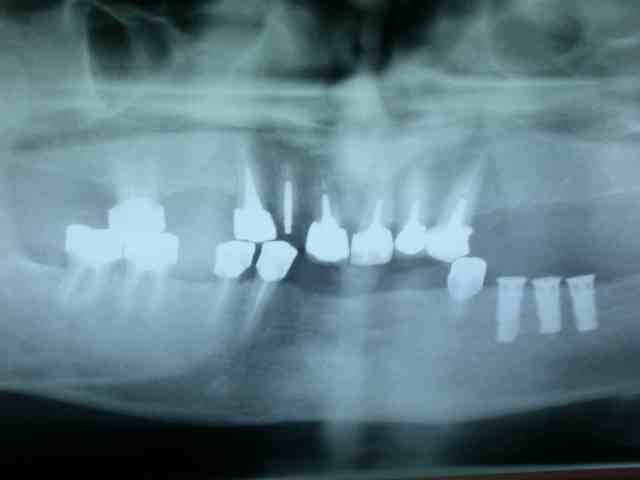

on évoluera par étapes :

1)mise en pace de 3 implants 35 36 37

2) on garde 34 pour stabiliser l'appareil

3)on attend l'ostéointégration des implants.

pano après